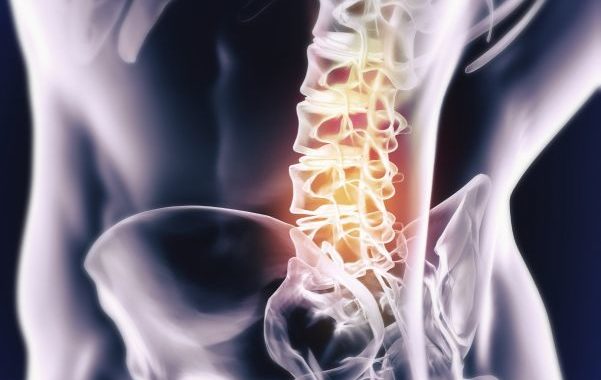

Central Nervous System Exam

Lumbo-Sacral Spine Exam

Low Back, Core, and Pelvic Girdle Treatment

- Prolo-acupuncture for lumbar facets, sacro-iliac and pubic symphysis joints, and iliolumbar and sacrotuberous ligaments

- Soft joint mobilizations for lumbar facets, sacro-iliac and pubic symphysis joints

- Trigger point needling, gua sha, and manual therapies for lumbar, abdominal and gluteal musculature, including quadratus lumborum and iliopsoas